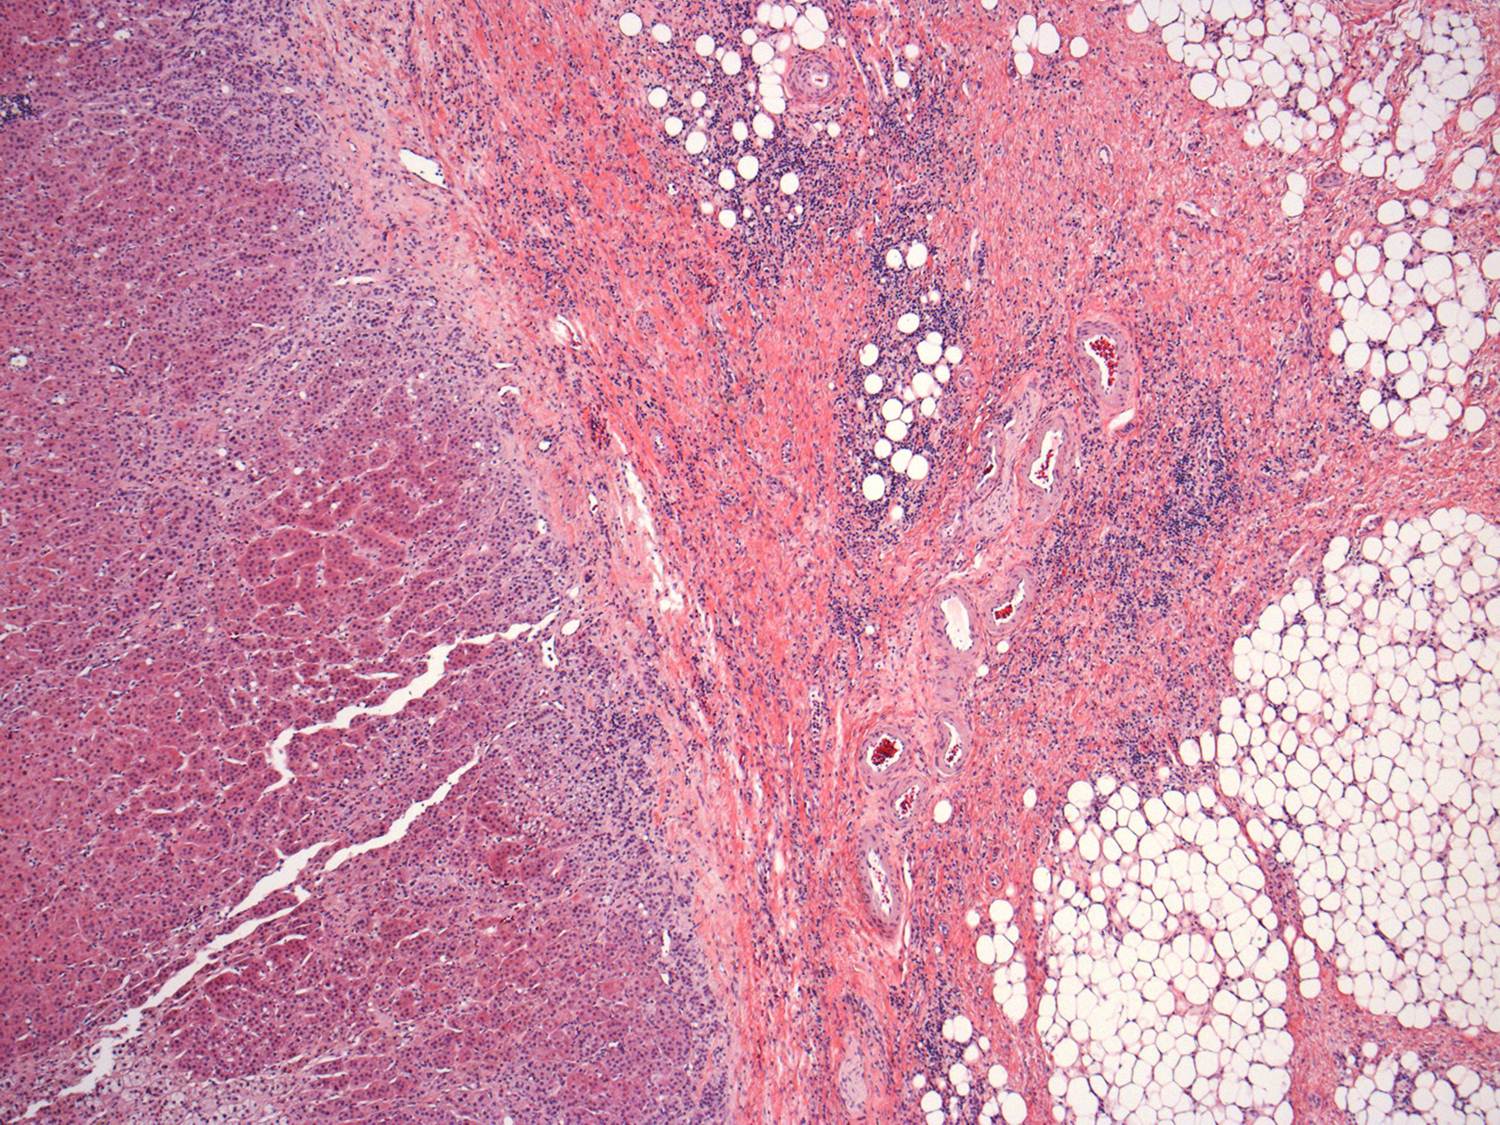

The adrenal gland was essentially normal apart from some focal inflammation and adhesion to the capsule. There was no evidence of any malignancy and it is likely that the changes seen were a result of infection which had resolved by the time of the surgery.